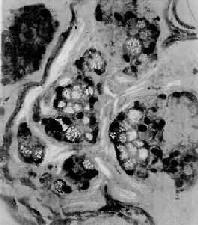

图10-19 粘液癌 癌细胞成团,胞浆内充满大量粘液,核被挤向一侧,呈印戒状 除上述分型外,也有根据胃癌细胞形态和胃癌组织中粘液性质将胃癌分为肠型和弥漫型两大类。肠型胃癌中唾液酸粘液及硫酸粘液多见,而弥漫型胃癌中中性粘液多见。肠型胃癌多见于老年患者,恶性度较低,组织学上多为乳头状腺癌或腺管状腺癌。弥漫型胃癌多见于青年人,恶性度较高,组织学上多为粘液癌及未分化癌。 需要指出,许多胃癌的组织学结构不是单一类型,在同一胃癌标本中往往有两种组织类型同时存在。发生在贲门部的胃癌,可为兼有腺上皮及鳞状上皮的腺棘皮癌(adenoacanthoma)及鳞状细胞癌。 【扩散途径】 1.直接扩散浸润到胃浆膜层的癌组织,可直接扩散至邻近器官和组织,如肝、胰腺及大网膜等。 2.淋巴道转移为胃癌转移的主要途径,首先转移到局部淋巴结,其中以胃小弯侧的胃冠状静脉旁淋巴结及幽门下淋巴结最为多见。由前者可进一步扩散到腹主动脉旁淋巴结、肝门处淋巴结而达肝内;由后者可到达胰头上方及肠系膜根部淋巴结。转移到胃大弯淋巴结的癌瘤可进一步扩散到大网膜淋巴结。晚期,癌细胞可经胸导管转移到锁骨上淋巴结,且以左锁骨上淋巴结多见。 3.血道转移多在晚期,常经门静脉转移到肝,其次可转移至肺、骨及脑。 4.种植性转移胃癌特别是胃粘液癌细胞浸润至胃浆膜后,可脱落到腹腔,种植于腹壁及盆腔器官腹膜上。有时在卵巢形成转移性粘液癌,称Krukenberg瘤。 【胃癌的组织发生】 1.胃癌的细胞来源从早期微小胃癌的形态学研究推测,胃癌主要发生自胃腺颈部的干细胞。此处腺上皮的再生修复特别活跃,可向胃上皮及肠上皮分化,癌变常由此部位开始。 2.肠上皮化生与癌变在早期胃癌标本可观察到肠上皮化生(大肠型)过渡到肠型胃癌的理象。大肠型化生在胃癌癌旁粘膜上皮的检出率常可达88.2%。有人推测癌变机制可能由于这种肠上皮化生的细胞对致癌物质的吸收增强,并且发现肠上皮化生细胞及癌细胞的胞浆中均有高活性的氨基酞酶(amino-peptidase),而正常胃粘膜中,该酶不显活性。这种变异很可能构成癌变的基础。 3.不典型增生与癌变 胃癌时重度不典型增生(severe atypical hyperplasia)多出现在癌旁,有的并与癌变呈移行关系。目前认为重度不典型增生为具有癌变潜能的一种癌前病变。 【病因】 至今未明。人类胃癌的发生有一定的地理分布特点。如在日本、中国、冰岛、智利及芬兰等国家的发病率远较美国及西欧国家为高。这可能与各国家、民族的饮食习惯及各地区的土壤地质因素有关。据调查,胃癌的发生和大量摄取鱼、肉类熏制食品有关。用黄曲霉毒素污染或含亚硝酸盐的食物饲喂动物也可诱发胃癌。在日本曾有人提出胃癌的高发与居民食用的稻米经滑石粉处理有关。因滑石粉内含有致癌作用的石棉纤维。近年,由于日本饮食习惯的改变,其胃癌的发生率有下降趋势。 【其它肿瘤】 平滑肌瘤胃肠是除子宫外的另一平滑肌瘤多发部位。其中,以胃为最多,其次是小肠。此瘤常可突入胃肠腔,也可呈巨大团块由浆膜向外突出,此时则不引起胃肠症状。肿瘤组织由交织的束状平滑肌细胞构成,细胞两端有长突起,胞核钝圆,也偶见圆形或多角形细胞。如瘤细胞是不典型或奇型的平滑肌细胞则称为平滑肌母细胞瘤。在组织学上区分平滑肌瘤及平滑肌母细胞瘤较为困难。后者虽有瘤细胞的不典型增生,但仍不能视为恶性。属于恶性的平滑肌肉瘤除显示多数瘤细胞核呈多型性并可有奇异形态的巨细胞外,较多的核分裂像也常是恶性的指征。平滑肌肉瘤常由血行转移,也可直接浸润、扩散到腹膜表面。 恶性淋巴瘤结外的恶性淋巴瘤最常发生在胃,其次为肠。胃之原发性恶性淋巴瘤在临床上甚难与胃癌区别。本瘤术后5年存活率较胃癌为高。外观,常呈扁平盘状突起,边缘清楚。有时肉眼上与癌难以区别。

图10-11 早期胃癌的脱落细胞 (与图10-10同一病例) 癌细胞较大,形状不一,核大,着色深 早期胃癌的肉眼形态可分为3种类型(图10-12): 1.隆起型(protruded type,Ⅰ型)肿瘤从胃粘膜表面显著隆起,有时呈息肉状。 2.表浅型(superficial type,Ⅱ型)肿瘤表面较平坦,隆起不显著。此型又可细分为:①表浅隆起型(superficial elevated type,Ⅱa型)(图10-13),②表浅平坦型(superficial flat type,Ⅱb型),③表浅凹陷型(superficial depressed type,Ⅱc型),又名癌性糜烂。